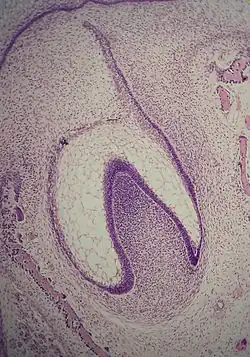

A: organe de l'émail avec la lame dentaire

B: papille dentaire

C: follicule dentaire.

La formation d'une dent commence donc par un agrégat cellulaire, le germe dentaire[2], dérivant de l'ectoderme issu du premier arc branchial de la crête neurale[1],[3],[4]. Ce tissu d'origine ectoblastique va se transformer en un tissu mésenchymateux appelé ectomésenchyme ou mésenchyme ectodermique. Le germe dentaire est divisé en trois parties : le bourgeon dentaire (ou organe de l'émail ou encore organe adamantin), issu de l'ectoderme, la papille dentaire et le follicule dentaire, issus du mésenchyme.